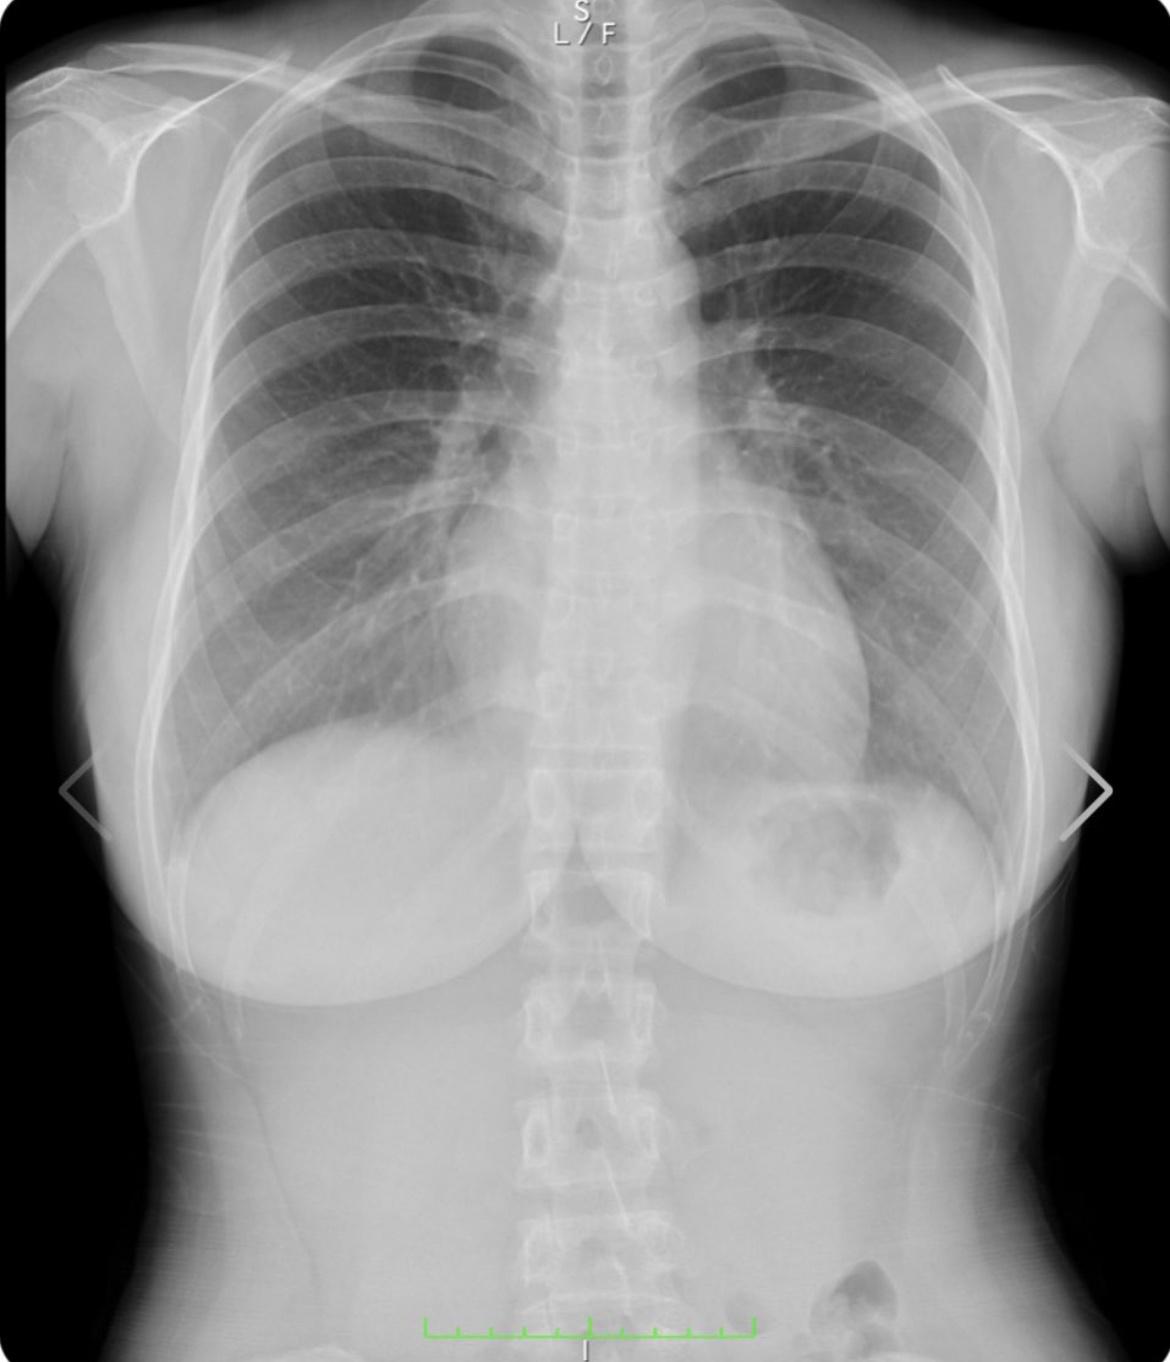

デカすぎんだろ…

すけすけのJC

すごい歪み方しとるやん